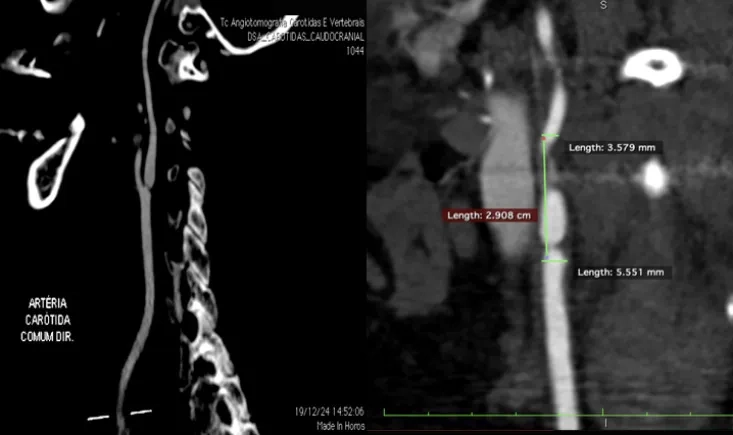

This PVI 2025 symposium replay examines post-CREST-2 carotid stenting through the case of a 71-year-old wom…